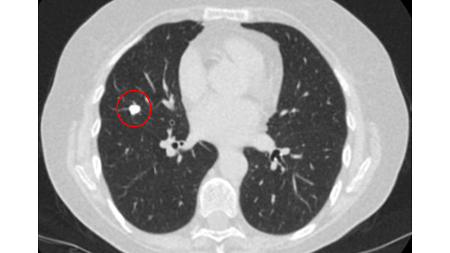

A dense central, laminated, chondroid pattern of calcification (often called popcorn calcification) or a diffuse pattern of calcification strongly suggests that a nodule is benign.[Figure caption and citation for the preceding image starts]: Computed tomography (CT) showing a benign calcified granuloma in the right middle lobe, stable >10 years. The patient reported previous pneumonia on the same sideFrom the collection of Dr George Tsaknis, MD, PhD, FRCP(London), MRQA, MAcadMEd, PGCert; used with permission [Citation ends].

A calculated likelihood ratio for malignancy with a benign pattern of calcification approaches zero.[19] Approximately 10% of malignant nodules have a non-benign pattern of calcification (see E and F).[26][Figure caption and citation for the preceding image starts]: A-D: calcification patterns of benign nodules; E, F: may be seen in malignant nodulesMazzone P.J., Stoller J.K. Semin Thorac Cardiovasc Surg. 2002;14:250-260; used with permission [Citation ends].